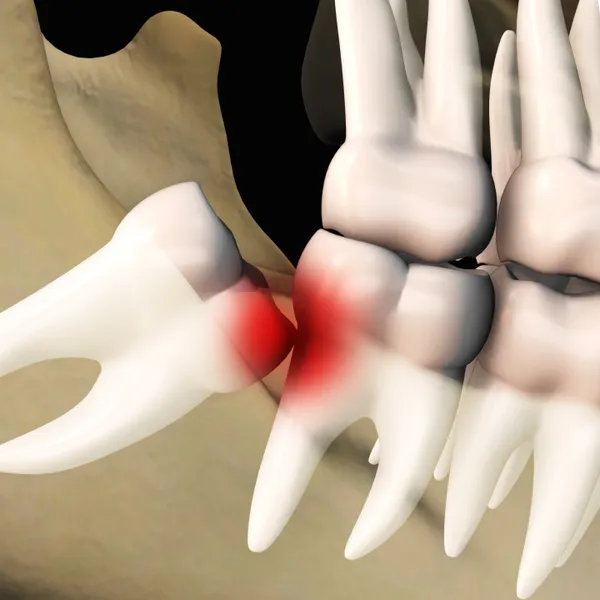

Wisdom teeth are the last set of molars that typically emerge in the late teens or early twenties. In many cases, these teeth can become impacted or grow in at an angle, leading to a range of dental issues.

Impacted or misaligned wisdom teeth can cause significant pain and infection.

Impacted wisdom teeth are prone to cavities and gum disease because their location makes them hard to clean.